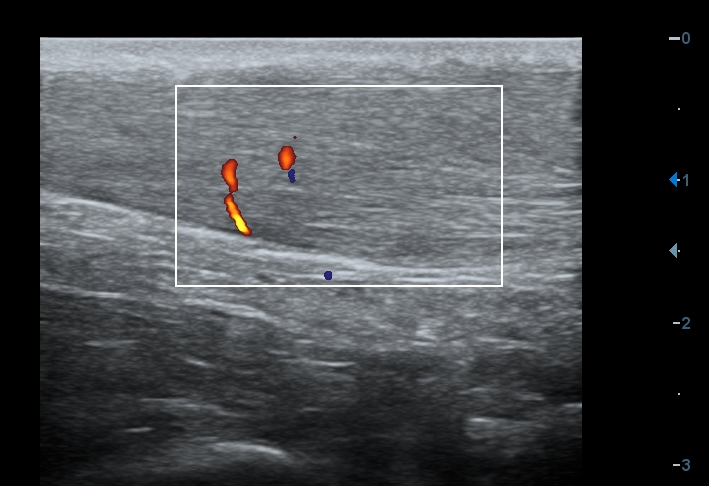

Obr. 2: Extrémně vřetenovitě rozšířená Achillova šlacha s prokázanou patologickou neovaskularizací